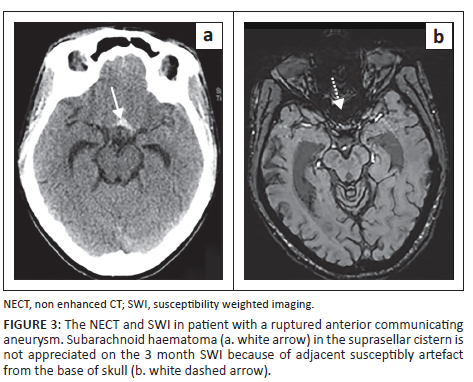

This study showed a sensitivity of 50% in the perimesencephalic cistern, exceeding that of previous studies with T2* of 8%.16 The poor sensitivity in this region was because of regional artefact from the base of skull and high CSF flow displacing any haemorrhage as depicted in Figure 3.12,13,16,17,18